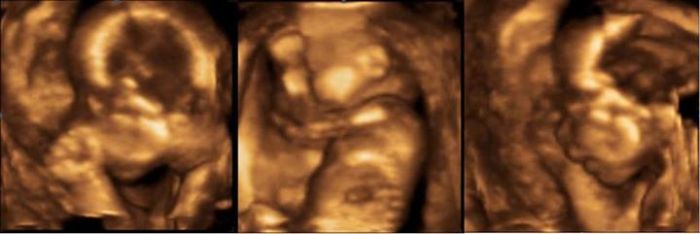

Holky krasne fotky jak briska tak utz :) ja osobne mam taky 8kg nahore a jsem 25tt, po pra nazorech co tu padly se teda s pritelem spokojujeme a zvykame si na holcicku :) vcera vecer dokonce pritel mluvil s briskem a rikal :) tebe jsem nechtel :) chtel jsem kluka :) o to vic si te pohlidam :) no jo bude to takova tatinkova princezna. Prikladam taky fotecku, ktera je z 20tt + 1d sice v tom furt vidim chlapecka :) ale i holcicka to bude fajn :) aspon tady to skore trosku u holcicek zvednu :) Co se tyce veder mi ani nemluvte, jsem furt zavrena doma a kdyz uz konecne vyjdu ven tak kolabuju, mam nizky tlak :(

Kačátko 87: to je sranda a člověk by už čekal, že to je "definitivní"...:) Takže holčička..:) Modrá jí bude taky slušet :) Z fotky si to teda netroufám odhadnout, jestli to fakt bude holčička, ale ta poslední 3D je mooc hezká :)

Ahojte holky :-) Včera jsem byla u doktora, nechala jsem si udělat nějaké 3D fotky mimča. Miminko má trochu větší nos, ale věřím, že mu k tomu ještě doroste obličejík :-D. Co mě ale znepokojilo je, že měl pupečník kolem krku. Doktor mi řekl, že teď to nic neznamená a dál se k tomu nevyjadřoval. Tak doufám, že se tam zase nějak odmotá no :-(. Jinak se mu asi daří dobře, protože vypadá o týden větší než má být :-) 800 g, to už je slušná váha :-D Akorát ten pupečník no...pořád nějaký stres :-(